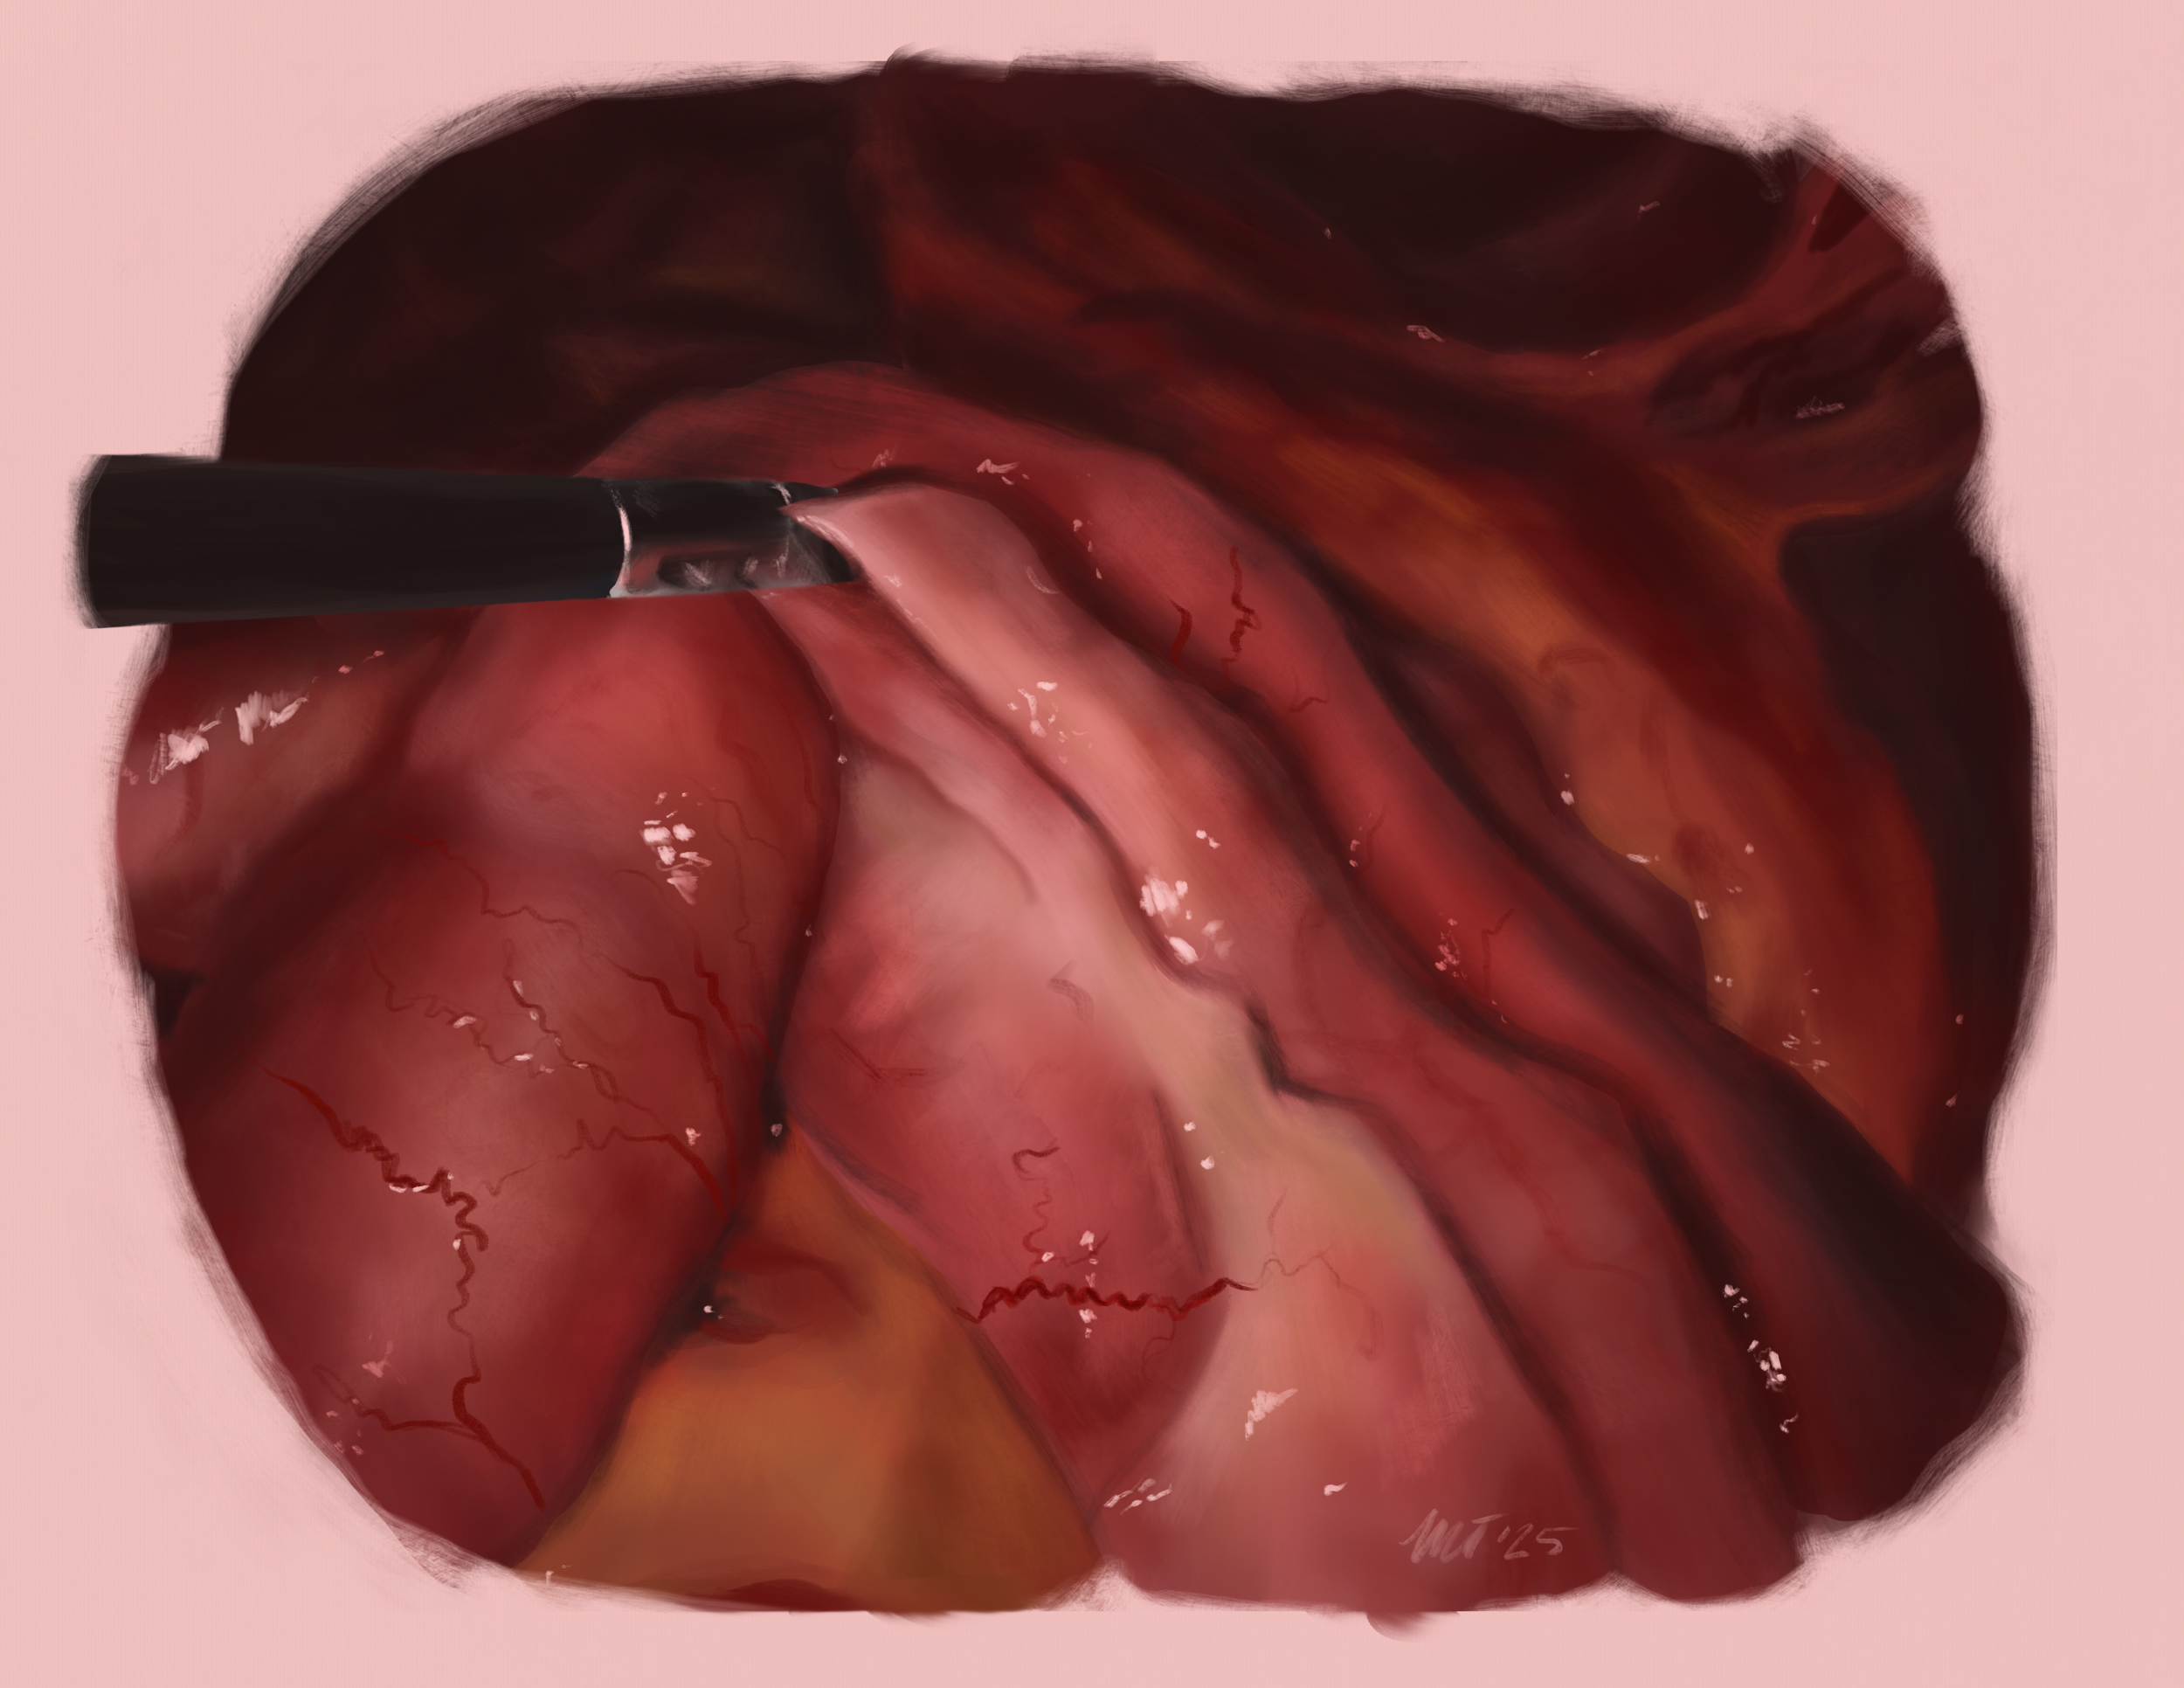

Tissue reaction study: Sleeve gastrectomy to Roux-en-y gastric bypass conversion